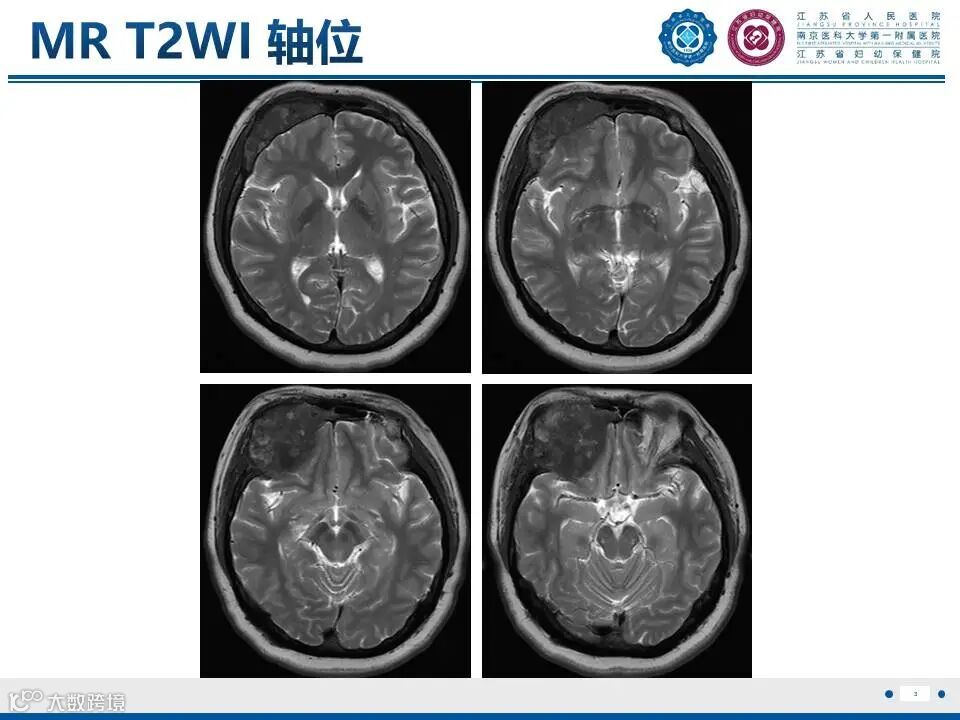

颅骨骨纤维异常增殖症——颅骨上的编织骨

颅骨骨纤维异常增殖症——颅骨上的编织骨 鼎湖影像